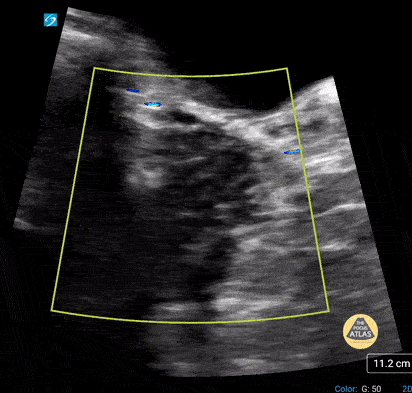

Normal Adolescent Ovary (transabdominal). Contributor: Paul Khalil, MD Nicklaus Children's Hospital @khalil3paul